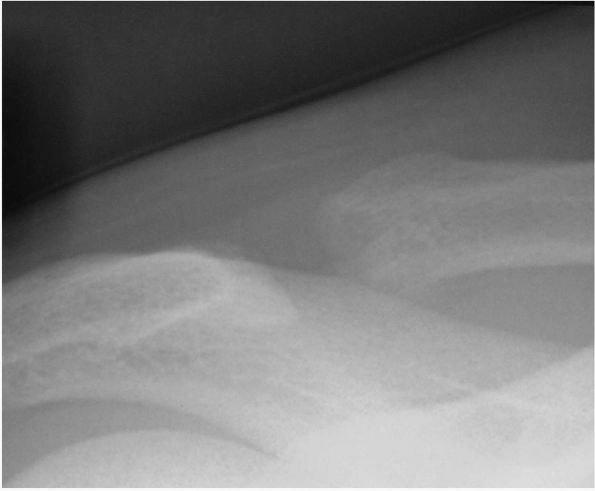

performed arthroscopically, the technique of arthroscopic distal

clavicle resection has become more common. Esch et al.

described a subacromial approach to excision of the distal clavicle in

patients undergoing a subacromial decompression procedure. A superior

direct approach to the AC joint was subsequently developed with the

theoretical advantage of preserving subacromial and capsular anatomy (Figure 12-4).

The advantages of either arthroscopic approach over open resection are

reduced morbidity with smaller incisions and avoidance of detaching the

deltoid and trapezius. However, more technical skill is required in

addition to the potentially higher risk of inadequate resection (Figure 12-5).

FIGURE 12-4. (A) Arthroscopic distal clavicle resection from a superior (direct) approach; (B) Resection of the distal clavicle viewed from the subacromial space.

|

![]() |

FIGURE 12-5. (A) and (B) Postoperative anteroposterior views after distal clavicle resection.